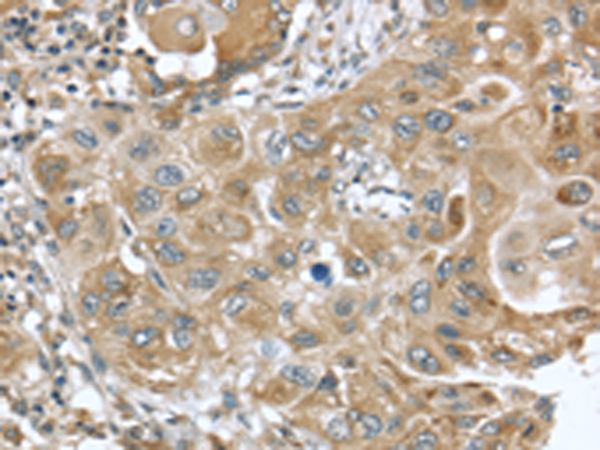

分类: 科研抗体货号: P08760别名: TID1; HCA57; hTID-1应用: IHC反应种属: Human, Mouse